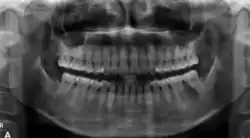

The radiographic features of central ossifying fibroma can be categorised according to the stages.

In its early stages, central ossifying fibroma (COF) appears as a small, well-defined radiolucent lesion due to its fibrous tissue content. Differential diagnoses at this stage include periapical pathology, central giant cell granuloma, and ameloblastoma.[22][23] As the lesion matures, it exhibits a mixed radiolucent-radiopaque appearance due to progressive calcification.[22] At this stage, it should be differentiated from other mixed jaw lesions such as fibrous dysplasia, calcifying epithelial odontogenic tumour, adenomatoid odontogenic tumour, and condensing osteitis.[22] In its mature form, COF may appear predominantly radiopaque, resembling lesions like odontomas, osteoblastomas, or osteosarcomas radiographically.

COF typically presents with well-defined, smooth, and often corticated borders. As a central lesion, it originates within the medullary bone and expands concentrically in all directions.[24] With growth, it may cause tooth displacement, root resorption, inferior displacement of the mandibular canal, and loss or alteration of the lamina dura of adjacent teeth.[25]

In conclusion, COF most commonly occurs in the mandible and expands from a central epicenter. Radiographically, it presents as a well-defined mixed-density lesion,[26] and Cone Beam CT (CBCT) plays a crucial role in its accurate diagnosis and assessment.